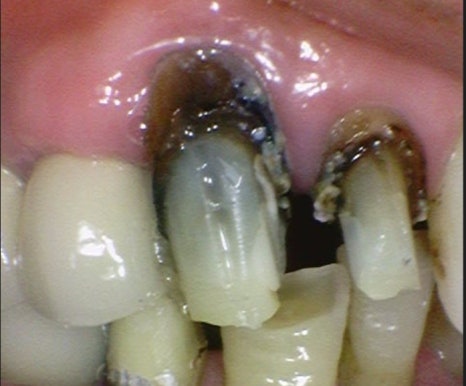

역시나...

내부는 충치가 많이 진행되어 있었습니다.

최대한 보존할 수 있는 치아를 남겨두고 충치를 제거한 후

튼튼한 재료로 보강을 하고 치아를 씌우기 위해 준비를 했습니다.